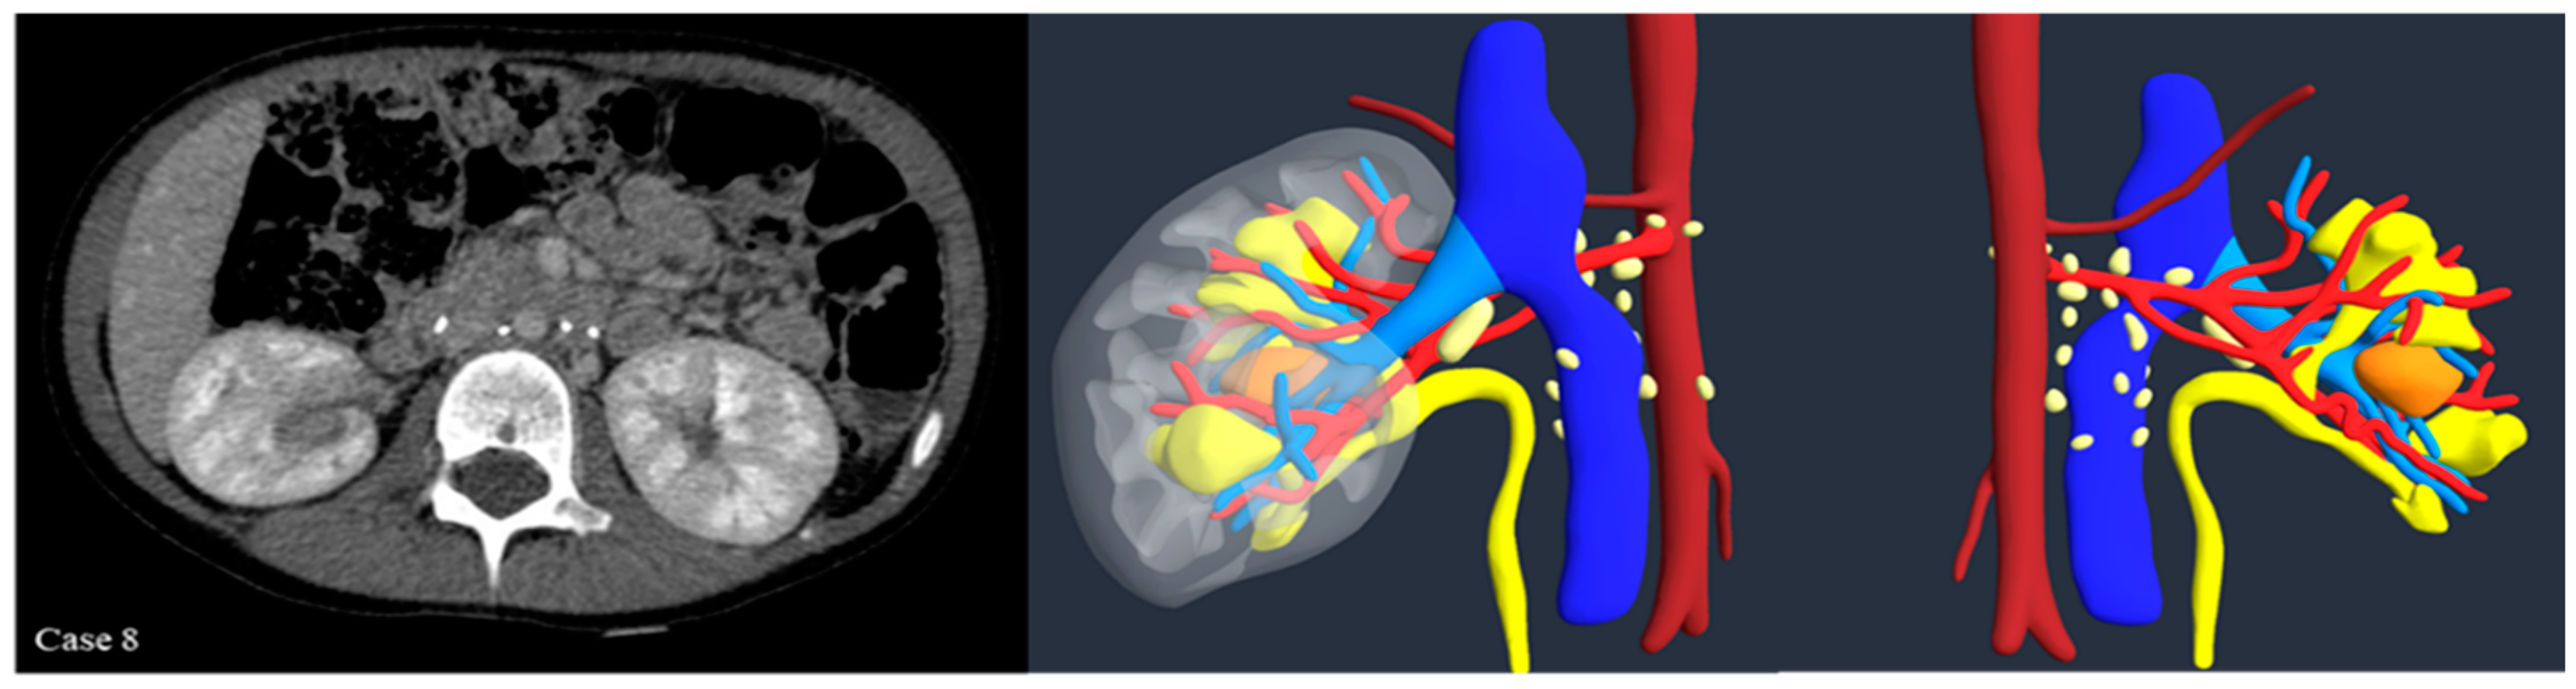

Introduction:The pre-operative planning for complex renal masses in children can be challenging, especially when nephron-sparing surgery (NSS) is recommended. We re-port our experience with the use of 3D-virtual reconstruction (3DVR) and its impact on surgical decision making. Materials and methods: Patients with complex renal masses underwent preoperative 3DVR. DICOM data were obtained from abdominal MRI and/or CT scans. 2D images segmentation was then performed. Three oncology surgeons were asked to individually evaluate each patient's preoperative MRI, CT and 3DVR. A questionnaire regarding the quality of conventional imaging compared to 3DVR was completed following surgery. Results: 8 patients (4♂,4♀) were included: Cases 1,2 and 4 were circumscribed tumours in the right upper pole, left lower pole (Bosniak cyst IV) and right mid-upper pole (Bosniak cyst IIF) respectively; Case 3 was a large hilar mass involving the whole kidney, unresponsive to chemotherapy; Case 5 and 7 were stage IV Wilms' tumour with venous thrombosis; case 6 was a left mid lower renal mass in a patient with WAGR syndrome and acute lymphoblastic leukae-mia (ALL) and case 8 was a recurrent central right WT after previous NSS in a child with Beckwith-Wiedemann syndrome(BWS). Four radical nephrectomies and three NSS were performed. In comparison to conventional imaging, the 3DVR models were judged to be superior by the expert reviewers for all anatomical structures except the urinary tract(p< 0.05). Conclusions: Our study suggests that 3DVR can be considered a useful tool in the pre-operative evaluation of children with complex renal masses and can facilitate NSS in selected patients.

| Case | 1 | 2 | 3 | 4 | 5 | 6 | 7 | 8 |

| Sex (M/F) | F | M | M | M | F | F | M | F |

| Age (months) | 48 | 180 | 14 | 178 | 50 | 42 | 28 | 52 |

| Weight (kg) | 15 | 50 | 9.4 | 70 | 18 | 10.8 | 13 | 17 |

| Side | Right | Left | Left | Right | Right | Left | Left | Right |

| Position | UP | LP | UP+MP+LP | MP+UP | UP | MP+LP | LP | LP |

| Volume (ml) at surgery | 33 | 24 | 597 | 23 | 421 | 63 | 136 | - |

| Syndrome | - | - | - | - | - | WAGR | - | BWS |

| MRI | X | X | X | X | X | X | X | X |

| CT scan | X | X | - | X | X | X | X | X |

| Vein Thrombosis | - | - | - | - | X | - | X | - |

| UCSI | - | - | - | - | - | X | - | - |

| Surgery | RAL NSS | RAL NSS |

Open nephrectomy | RAL NSS | Open Nephrectomy | Open Nephrectomy | Open Nephrectomy | - |

| Operative time (minutes) | 210 | 200 | 240 | 150 | 450 | 310 | 320 | - |

| Histology | WT | TRCC | CN | CN | WT | WT | WT | - |